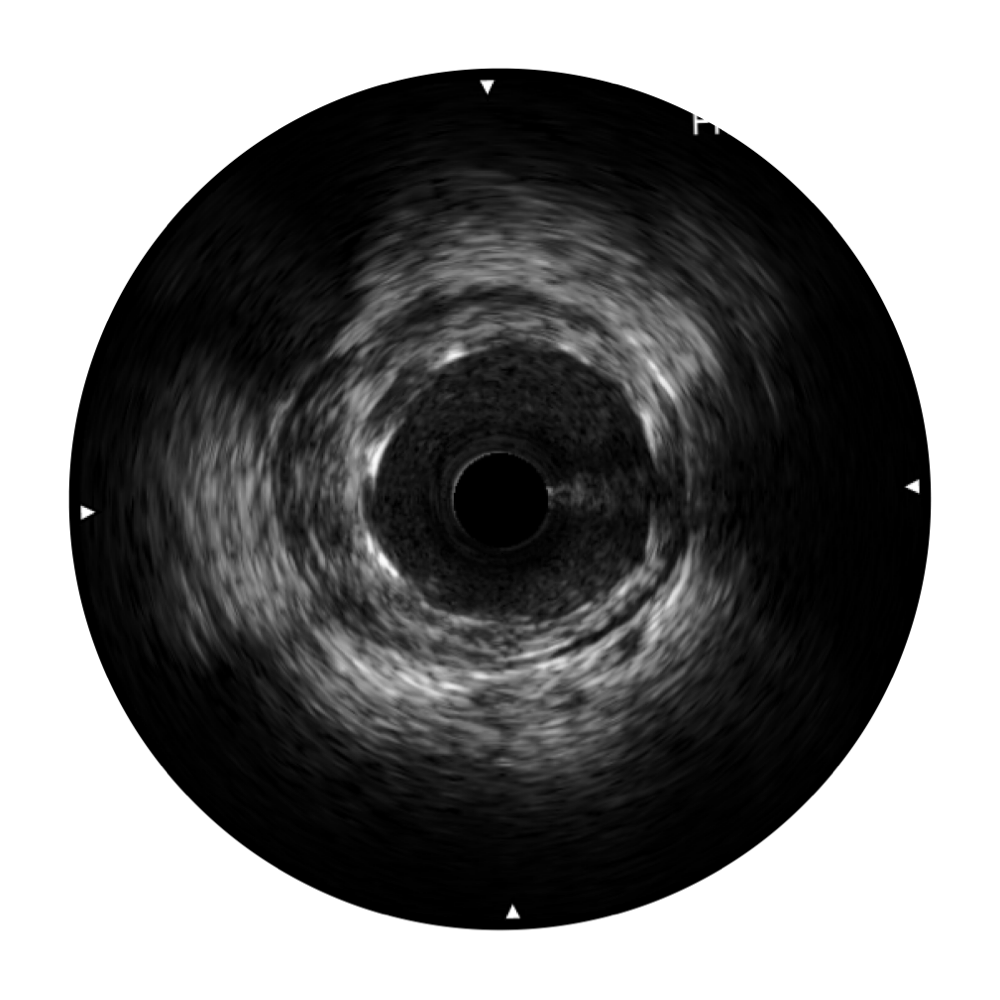

乐玩lewin国际宽频IVUS图像

对比传统IVUS导管成像,乐玩lewin国际宽频IVUS图像的近场支架梁显影更细腻,远场中膜外血管仍清晰可辨,兼顾远中近,兼顾分辨力与穿透深度